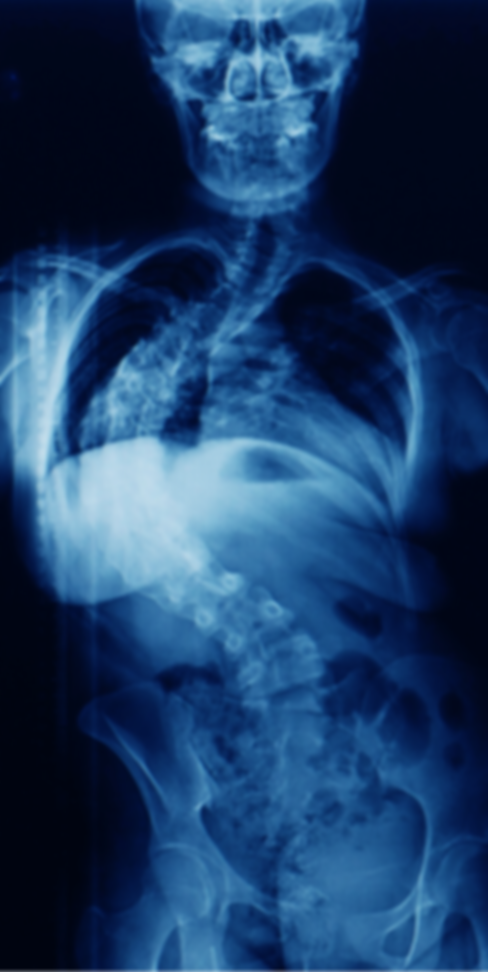

除了体检之外,影像学检查也可用于更准确地诊断脊柱侧凸。最常用的影像学检查是整个脊柱的站立 X 光检查。 X 射线使医生能够测量脊柱侧凸的精确曲率和程度。它们还提供有关椎体形状和排列的信息。

体检和影像学检查完成后,医生分析结果以做出准确的诊断。 X 射线和 MRI 扫描的测量和评估可以确定弯曲程度、预测脊柱侧凸的进程并制定个性化治疗计划。